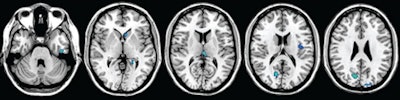

The study's longitudinal volumetric analysis showed a significant reduction in global gray-matter volume, while the VBM analysis showed the development of regional gray-matter atrophy in several cortical and subcortical regions in both hemispheres. There was no significant longitudinal change in global or regional white-matter fractional anisotropy.

| MR images show regions of decreased gray-matter volume at one-year follow-up in patients with clinically isolated syndrome (CIS). Significant clusters (light blue) of CIS are overlaid on the brain axial sections. Scattered volume reductions are found in several cerebral gray-matter regions, including the thalami, cuneus, paracentral lobule, insula, temporal cortex, caudate head, and supplementary motor areas. Images courtesy of Radiology. |

"It is beyond dispute that the correlation between the one-year follow-up gray-matter volumes and the baseline fractional anisotropy of white matter in our patients is strong," Raz and colleagues wrote. "Gray-matter atrophy increased significantly during the first year after the clinical onset of multiple sclerosis, whereas white-matter damage, which is present from the beginning, did not change significantly in the same time interval."